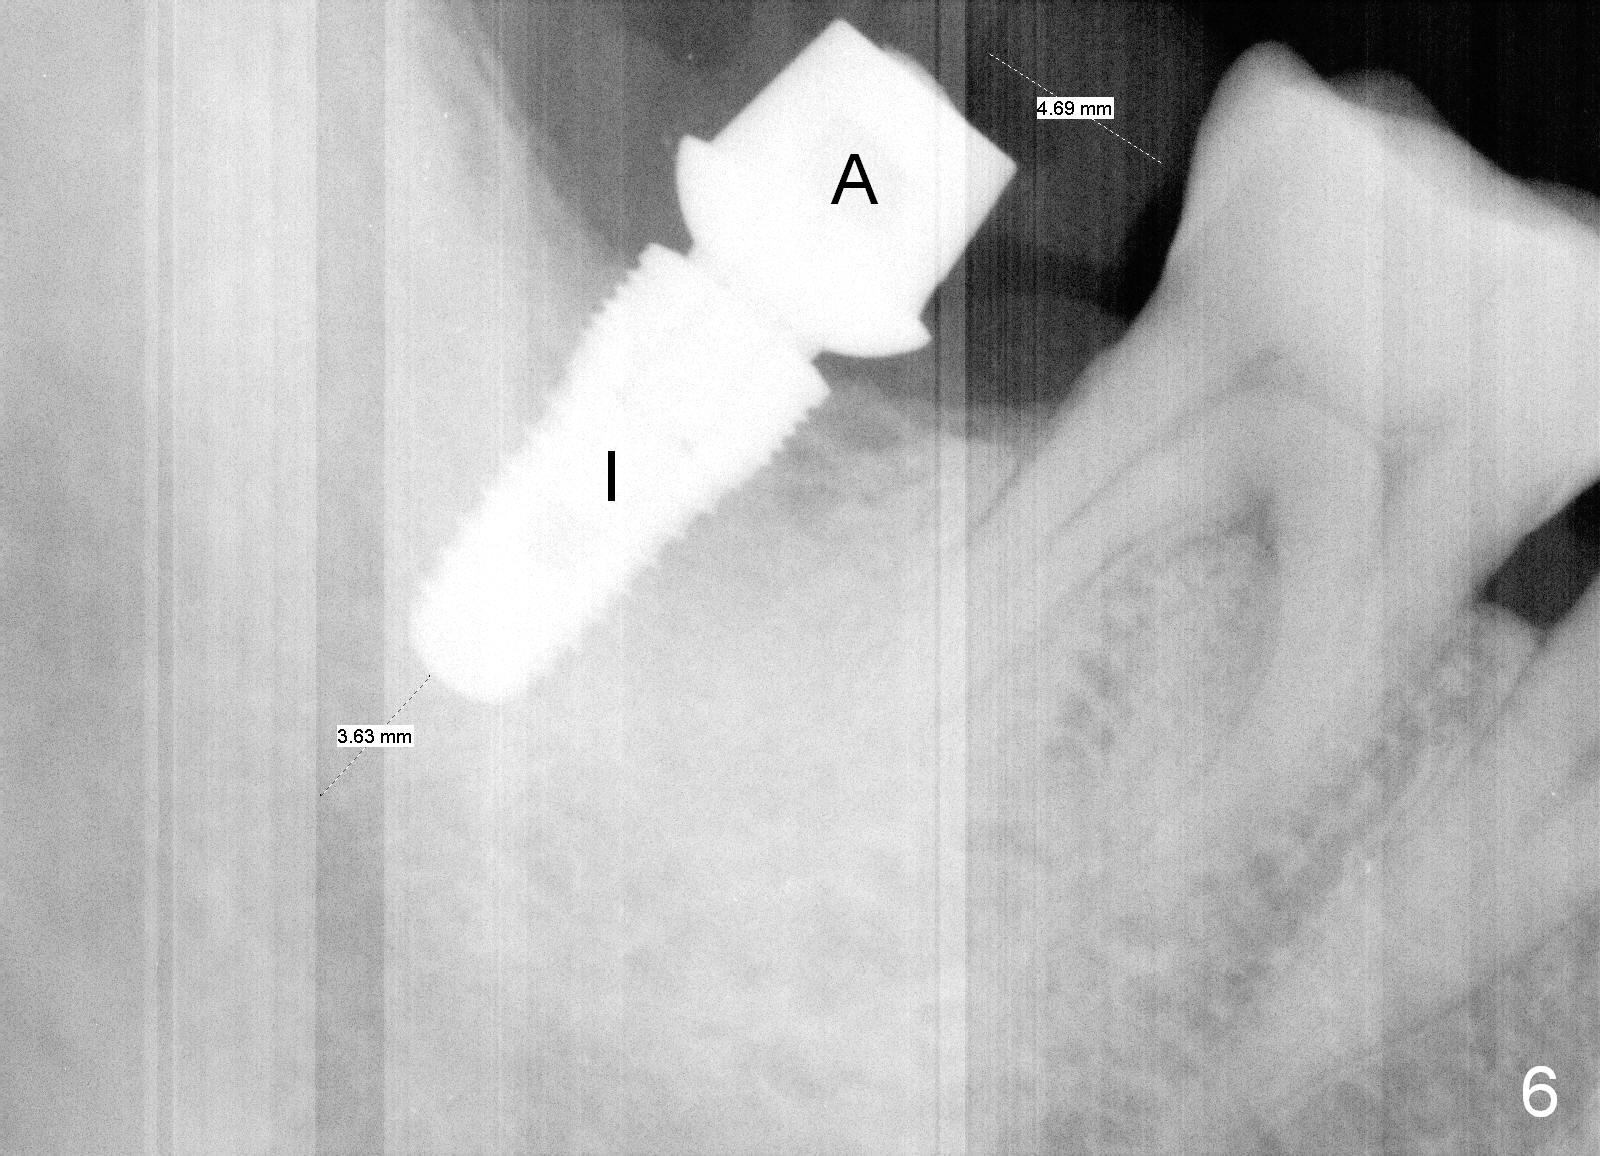

There appears to be bone loss coronally 15 months postop (Fig.8). There is no bone loss 1 year post cementation (2 years 3 months postop, Fig.9). If the implant were longer, it might perforate the lingual (L) plate (Fig.10 (1.5 years post cementation)).